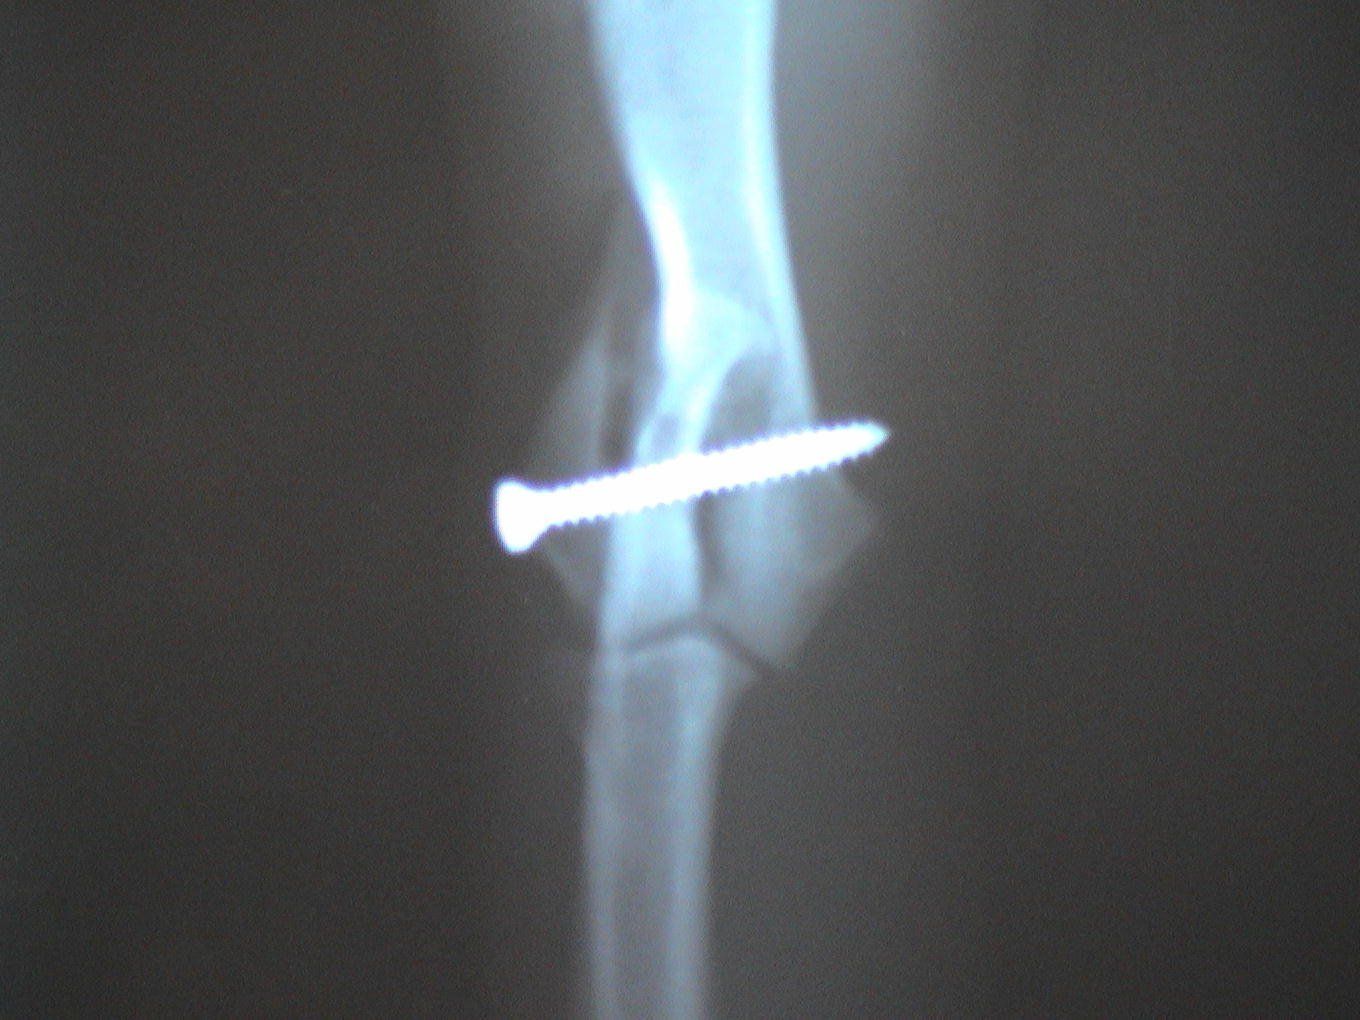

Dogs and cats commonly experience fractures secondary to trauma. The most common cause of the trauma is being hit by a car. Other trauma such as falls from furniture, jumping on unstable surfaces, leaping from a person's arms, etc. can also result in fractures. Below are some x-rays of some of the fractures we have seen at All Pets and their surgical correction using pins, plates, screws, and/or wires.